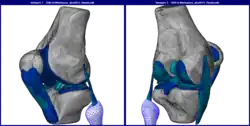

FEA may be used for analyzing problems over complicated domains (e.g., cars and oil pipelines) when the domain changes (e.g., during a solid-state reaction with a moving boundary), when the desired precision varies over the entire domain, or when the solution lacks smoothness. FEA simulations provide a valuable resource, as they remove multiple instances of creating and testing complex prototypes for various high-fidelity situations.[4] For example, in a frontal crash simulation, it is possible to increase prediction accuracy in important areas, like the front of the car, and reduce it in the rear of the car, thus reducing the cost of the simulation. Another example would be in numerical weather prediction, where it is more important to have accurate predictions over developing highly nonlinear phenomena, such as tropical cyclones in the atmosphere or eddies in the ocean, rather than relatively calm areas.

Various specializations under the umbrella of the mechanical engineering discipline (such as aeronautical, biomechanical, and automotive industries) commonly use integrated FEM in the design and development of their products. Several modern FEM packages include specific components such as thermal, electromagnetic, fluid, and structural working environments. In a structural simulation, FEM helps tremendously in producing stiffness and strength visualizations and minimizing weight, materials, and costs.[30]